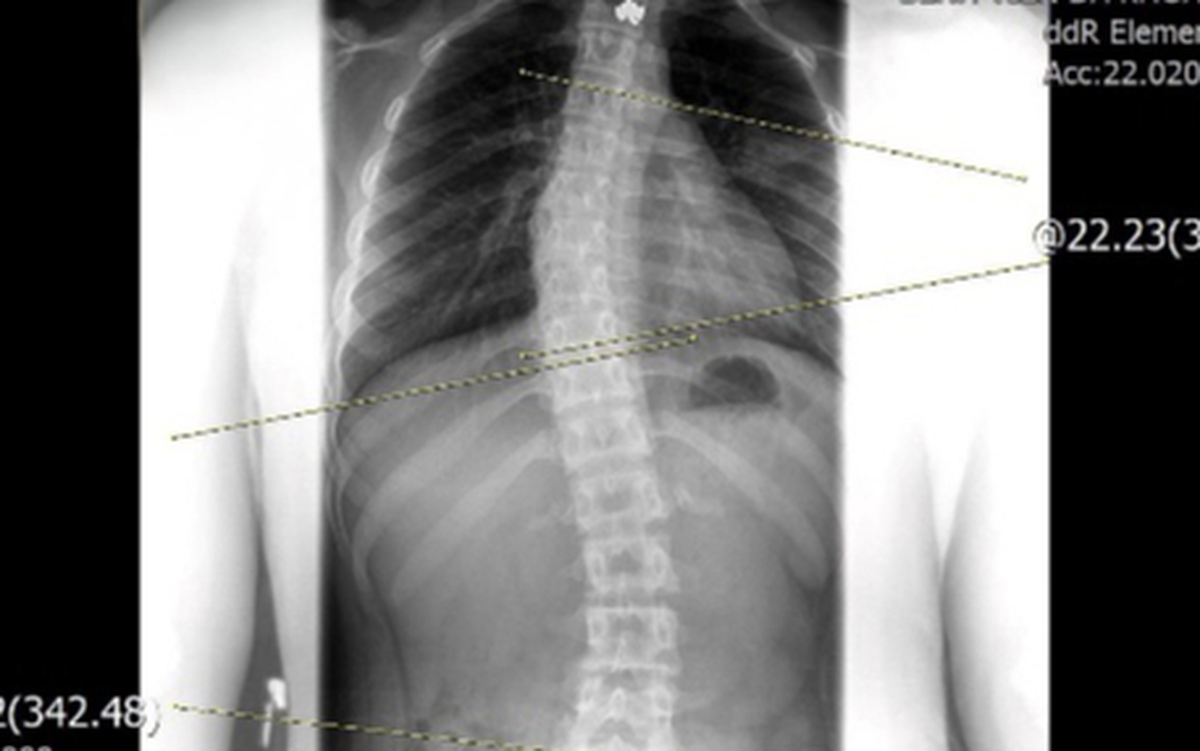

Chỉnh dáng cho trẻ vẹo cột sống bằng cách nào?